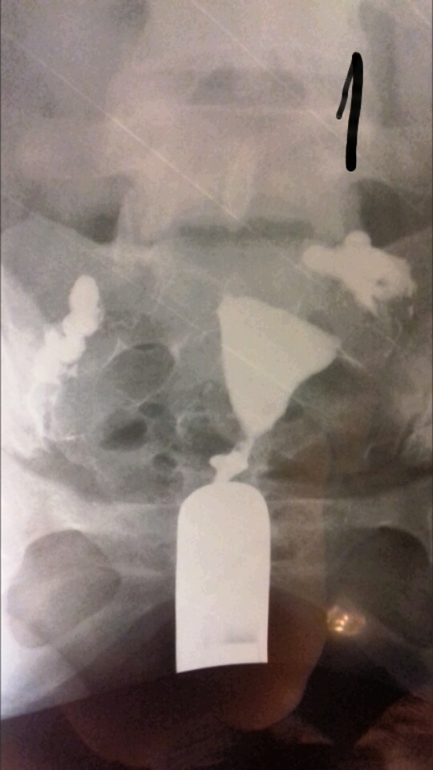

Лапароскопия, гистероскопияДобрый день девочки. Не знаю раздел куда написать, но думаю сюда. Сделала я гсг проверку труб рентгеном. Жидкость прошла, но не сразу, минут так 5 думаю лежала, хотя может меньше. Показало спайки в брюшной полости и вроде как в ампулярных отделах, так как они были расширены при поступлении контраста. И также сказали, что спайки скорее всего из-за эндометртоза. Кто сталкивался с такими проблемами, может подскажите, что по этому и по снимкам.

Полностью согласна. Все эти процедуры ведут только к лапаре. И гистероскопия также проводится в диагностических целях. Ну пробьют они раствором трубы, но это я думаю особой пользы не приносит. На снимках видно, что жидкость изливается в брюшную полость, значит проходимость есть, но если частичная, это уже не то. Так что не тчните, ларара, пару месяцев если еб нет и на Эко.